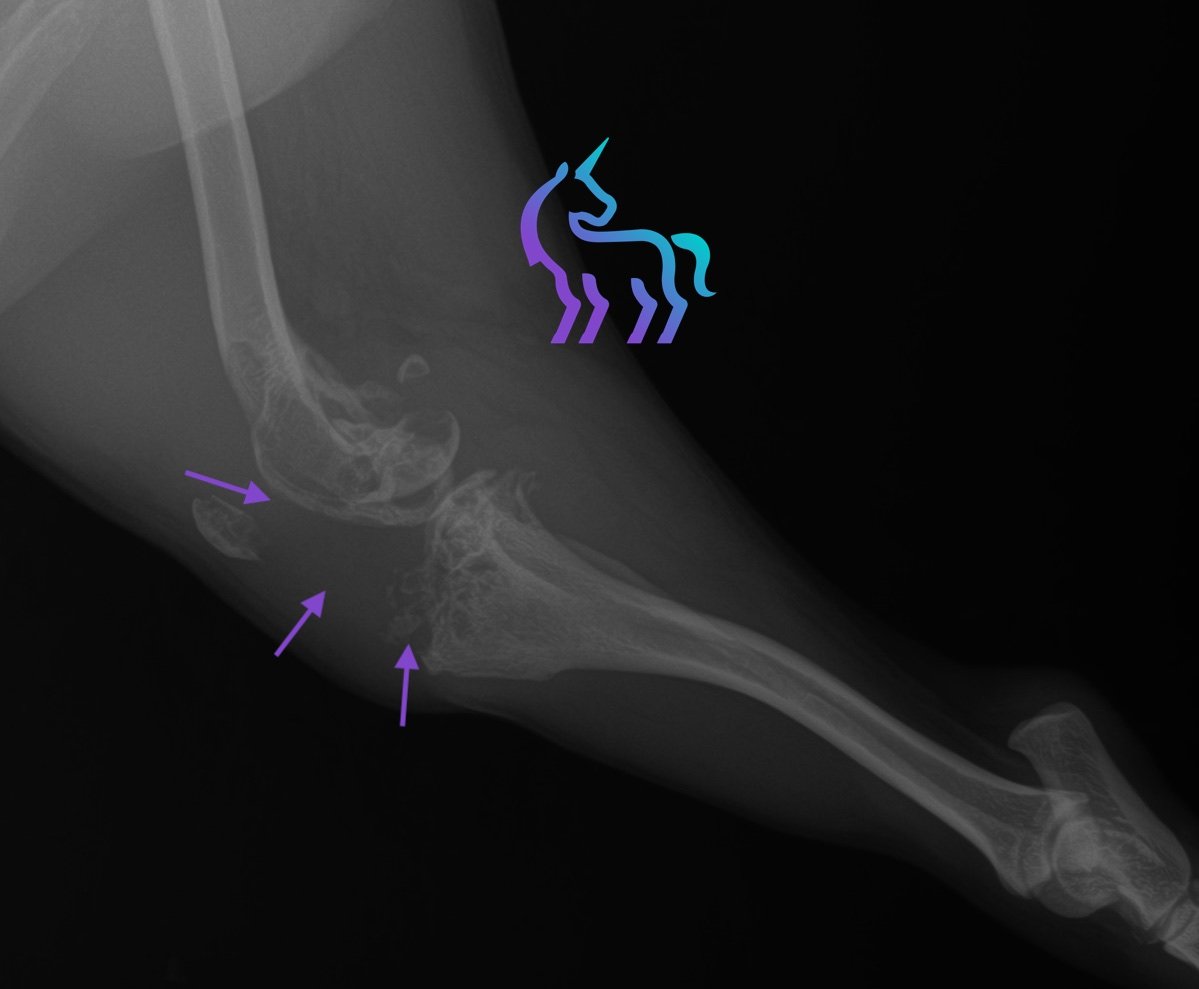

Processus tumoral ostéo-articulaire du grasset droit

Espèce : ChienRadiographies du grasset droit montrant une masse ostéolytique articulaire associée à une tuméfaction des tissus mous, sans métastase pulmonaire visible au bilan thoracique.

L’aspect est compatible en priorité avec un sarcome articulaire (notamment sarcome histiocytaire).

Diagnostic retenu : La radiographie permet ici de poser un diagnostic de tumeur osseuse agressive du grasset et d’orienter la prise en charge thérapeutique.